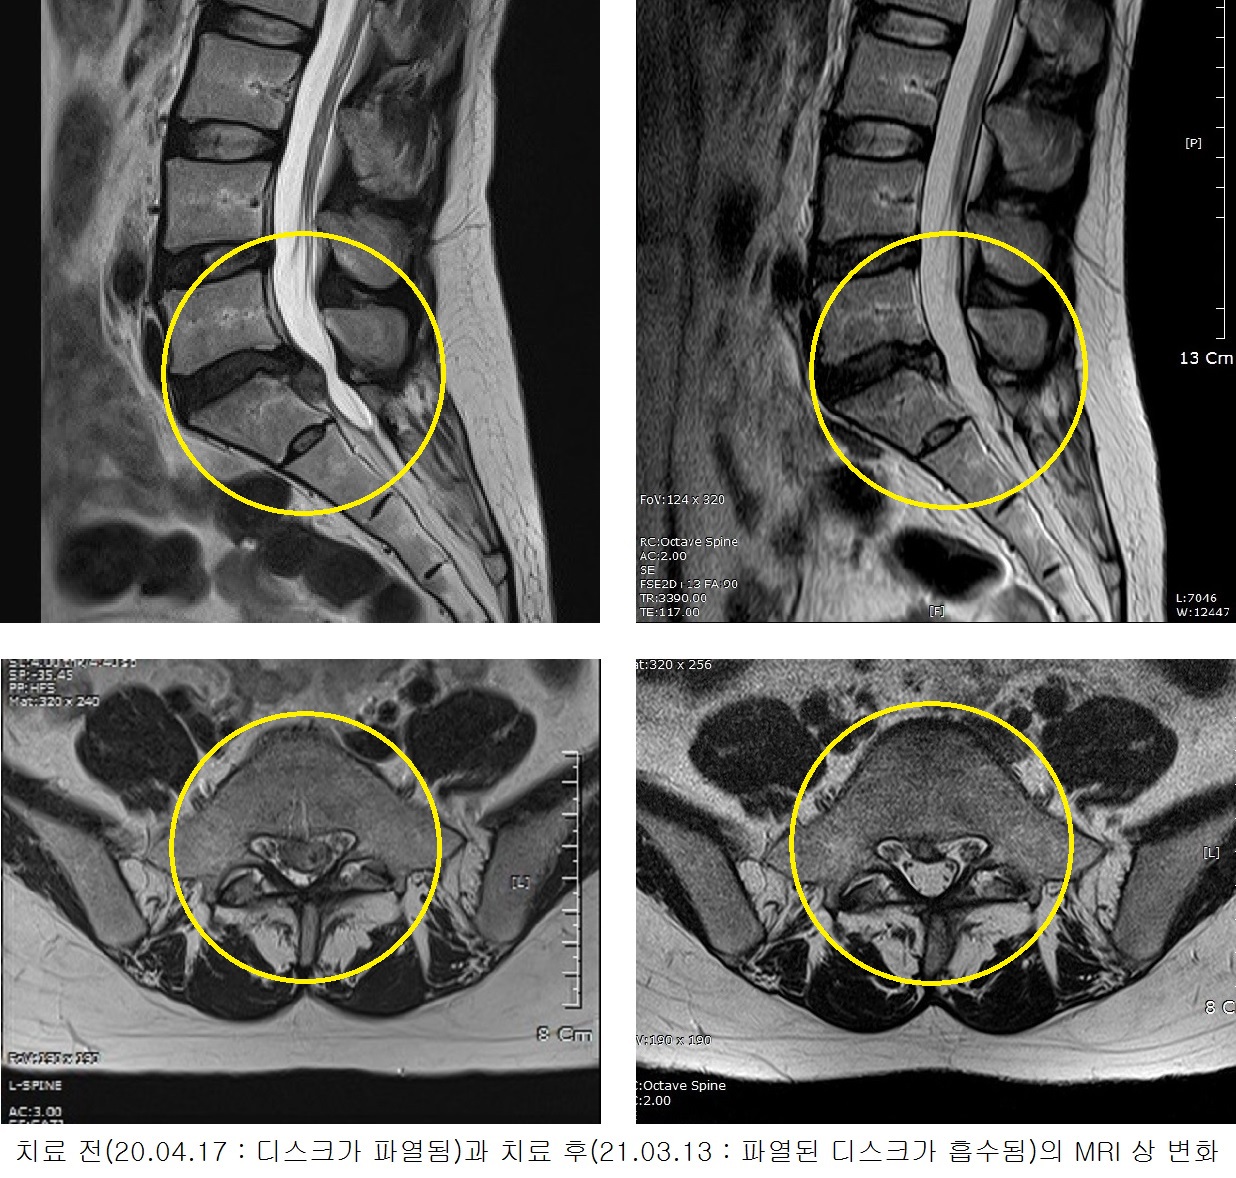

허리가 매우 아프고 오른쪽 다리가 찌릿거려서 제대로 못 서고 절뚝거렸다.

허리디스크 파열과 협착증으로 걷기조차 힘들고 의자에 앉을 수도 없었다.